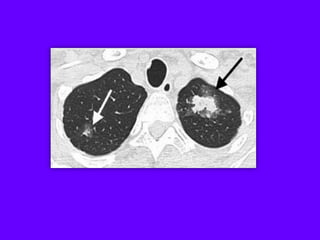

Langerhans Cell Histiocytosis

HRCT Findings

Small peribronchiolar nodules (1-5mm)

Thin-walled cysts (< 1cm),

Bizarre and confluent

Ground glass opacities

Late signs: irreversible / parenchymal fibrosis

Honey comb lung, septal thickening,

bronchiectasis

1 year later

Peribronchiolar Nodules Cavitating nodules and cysts

Langerhans Cell Histiozytosis

Key Features

Upper lobe predominance

Combination of cysts and noduli

Characteristic stages

Increased Lung volume

Sparing of costophrenic angle